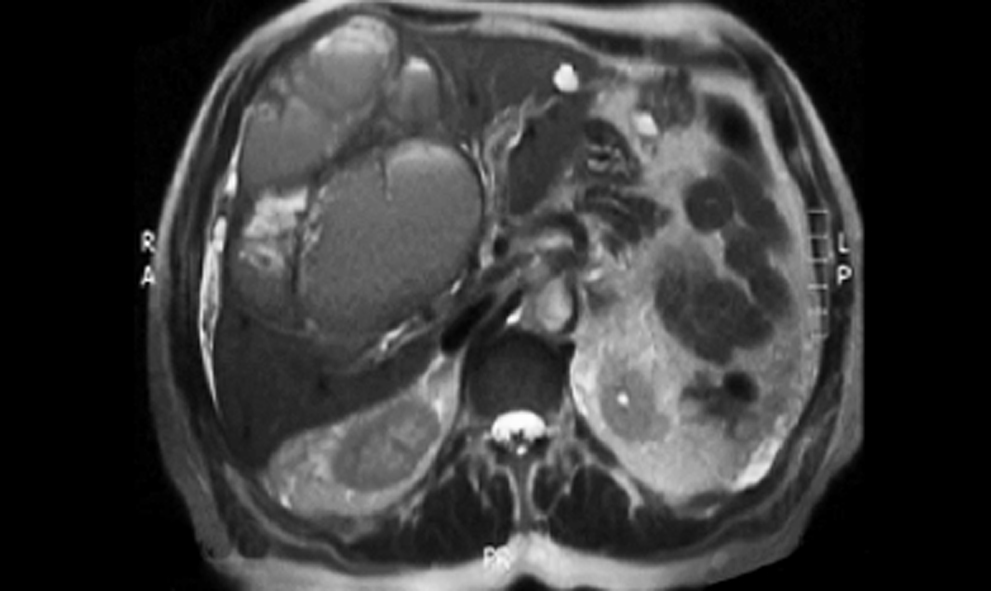

Hombre de 75 años de edad, sin antecedentes ni comorbilidades de importancia, con padecimiento de seis meses de evolución, el cual se manifestó por astenia, adinamia, dolor abdominal localizado en mesogastrio e hipocondrio derecho, y pérdida no intencionada de peso de hasta 15 kilogramos. A la exploración física se identificó tumor palpable en la región subcostal derecha de 12.0 x 9.0 cm, por lo que se le envió al servicio de gastrocirugía de un hospital de especialidades de tercer nivel de atención, en donde se inició un protocolo de diagnóstico. Se le realizó tomografía axial computarizada (TAC) toracoabdominal, se reportó colección hepática de segmento IV y una lesión nodular en segmento II de 2.9 x 2.7 cm, hipodensa y con reforzamiento al medio de contraste. En el estudio de resonancia magnética (RM) se identificó lesión localizada en lóbulo hepático derecho, la cual involucró los segmentos V, VI y VIII, multilobulada, con márgenes poco definidos, de contenido heterogéneo, con áreas quísticas, hiperintensa en T1 y T2, y con reforzamiento del componente sólido (figura 1). En la panendoscopía no se encontró evidencia de lesiones tumorales. En la correlación clínica radiológica se integró la sospecha diagnóstica de cistoadenoma seroso biliar. Ante la persistencia de la sintomatología se programó al paciente para la realización de laparotomía diagnóstica.

El diagnóstico de TNEPH es un diagnóstico de exclusión, como ya se apuntó antes.2,10,12Debe hacerse una búsqueda gradual y meticulosa, para determinar si hay un tumor primario extrahepático, comenzando con la realización de estudios de imagen, como ultrasonograma (USG), TAC, RM, octreoscan, endoscopia alta y baja, y laparotomía diagnóstica.2,10 El USG abdominal, aunque es poco específico, a menudo suele mostrar lesiones de aspecto sólido-quístico, hipoecogénicas, hiperecogénicas o mixtas. La TAC también revela nódulos hipodensos con degeneración quística, necrosis y calcificaciones. La RM mostrará lesiones hipointensas en T1 e hiperintensas en T2. Estas imágenes tienen un amplio espectro en su apariencia y a menudo imitan neoplasias hepáticas benignas y malignas, tales como colangiocarcinoma, carcinoma hepatocelular o metástasis, por lo que se complica el diagnóstico imagenológico.2,10,11 Esto explica la consideración diagnóstica de cistoadenoma seroso biliar que fue planteada en el paciente. Posterior al diagnóstico histopatológico se realizó una búsqueda intencionada y minuciosa de tumor extrahepático, que resultó sin evidencia de neoplasia.